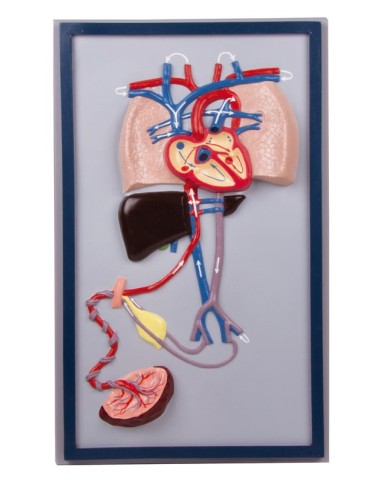

Kit composto da 3 modelli

Su Base, staccabile

Con scheda descrittiva dettagliata

Questo modello dettagliato mostra, oltre alle strutture anatomiche del cuore, anche una parte del diaframma (base)

Su tavola, con supporto e istruzioni per l'insegnamento. Con colorante rosso e siringa di riempimento.